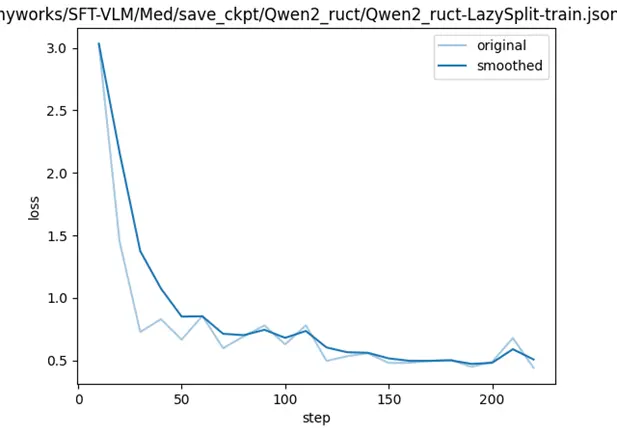

- 微調loss曲線

- 模型評測